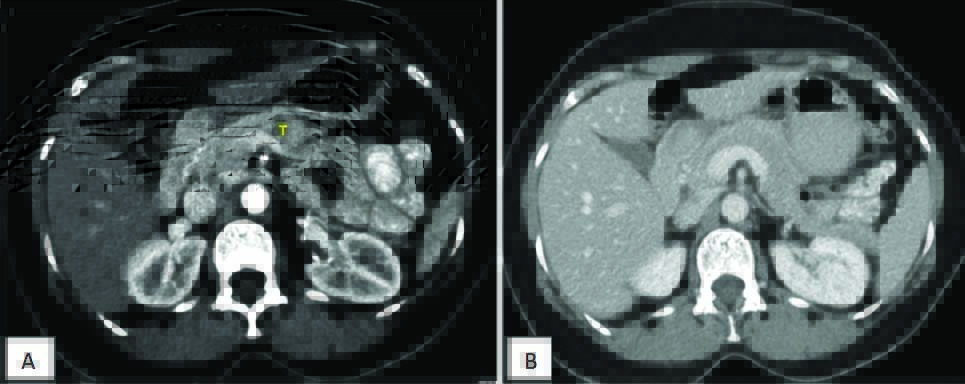

Contrast enhanced CT axial images depicts the importance of pancreatic protocol, image A shows pancreatic phase with pancreatic lesion “T” well visualized, which cannot be clearly made out in Image B which is acquired in venous phase.